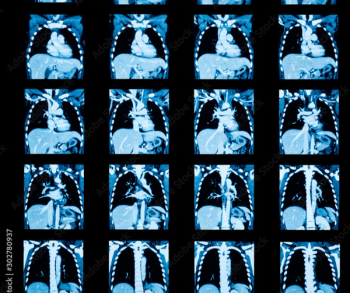

The advisory emphasizes that the computer-aided triage and notification (CADt) devices, many of which incorporate artificial intelligence (AI) or machine learning technology, are intended to aid radiologists in prioritizing the assessment of brain imaging that may reveal signs of large vessel occlusion (LVO).